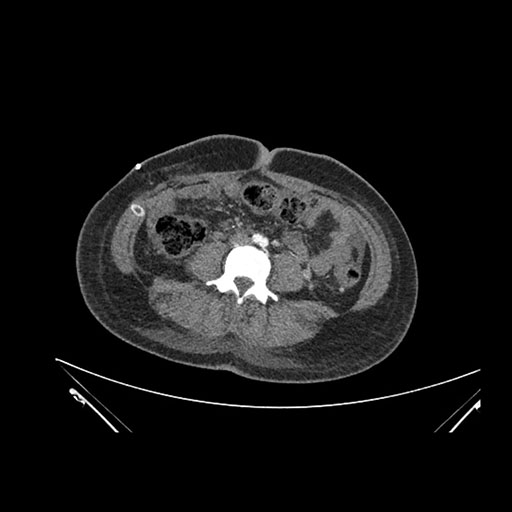

Imaging Analysis

Look through the patient's CT scan to identify any areas of concern for the necessary procedure.

Axial Arterial

Axial Venous

Based on initial findings, which issue(s) would you be most concerned about?